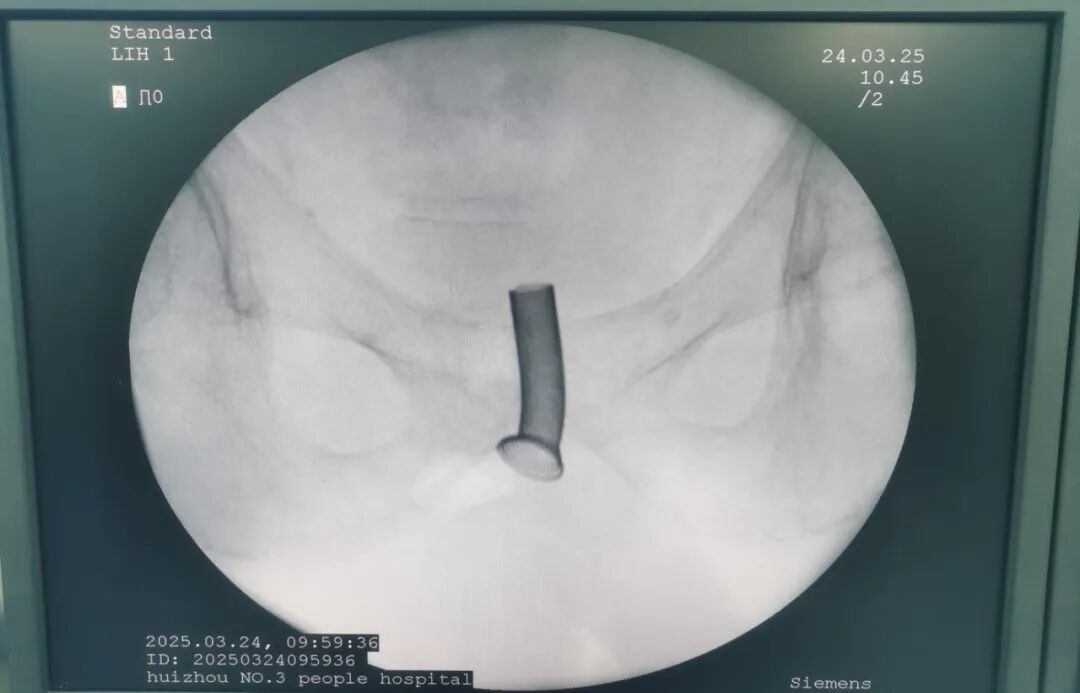

然而年后,患者膀胱残余尿逐渐增多,反复出现泌尿系感染,于是再次向惠州市第三人民医院泌尿外科二区主任岳峰博士求助。岳峰主任综合考虑患者的病情,并兼顾患者“微创,术后不影响生活质量”的需求,最终决定为其采用国产新型尿道热膨胀金属支架,实施前列腺金属支架置入术。

在医务部与临床多部门的密切协作下,手术顺利进行。术中,医护团队对病人进行全尿道浸润麻醉,其后进行膀胱镜镜检,计算前列腺梗阻长度,继而选择合适的尿道支架型号,并组装尿道支架及输送系统。

岳峰主任指出,支架植入手术十分适合这类高龄高危、合并基础疾病的排尿困难男性患者,这个支架可以理解为在病人体内植入一个能长期留置体内的导尿管,通过膀胱镜将支架放置在尿道的病灶狭窄部位,只需要表皮麻醉即可进行手术,帮助病人恢复正常的尿流通道,属于老年人适应性治疗技术。